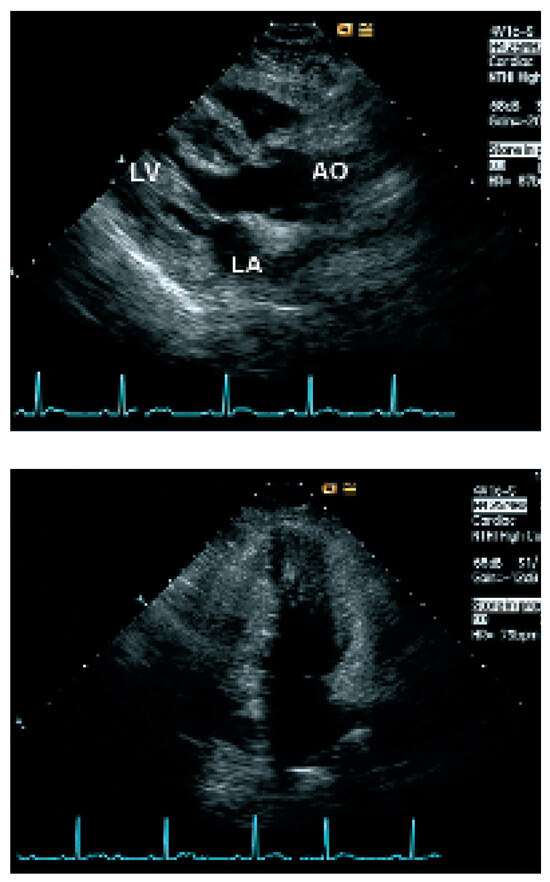

Update on Left Ventricular Hypertrophy

by Christina Attenhofer Jost

Detection and evaluation of left ventricular hypertrophy of unknown etiology by echocardiography is important in every cardiology practice. Causes of left ventricular hypertrophy include sarcomeric protein disorders (classical hypertrophic cardiomyopathy), metabolic disease (glycogen storage disease including LAMP2 deficiency, PRKAG2 mutations, Fabry disease), syndromic [...] Read more.

Detection and evaluation of left ventricular hypertrophy of unknown etiology by echocardiography is important in every cardiology practice. Causes of left ventricular hypertrophy include sarcomeric protein disorders (classical hypertrophic cardiomyopathy), metabolic disease (glycogen storage disease including LAMP2 deficiency, PRKAG2 mutations, Fabry disease), syndromic hypertrophic cardiomyopathy (Noonan’s syndrome, LEOPARD syndrome, etc.) and miscellaneous causes including systemic hypertension, amyloidosis, athlete’s heart and pheochromocytoma. Although there are several echocardiographic changes quite typical for some of the disorders, most changes are not 100% specific. ECG findings and symptoms provide important additional information. Genetic testing is increasingly important. Nowadays, a combination of ECG findings, symptoms, family history, genetic testing and findings of echocardiography provide the best means for differentiation of left ventricular hypertrophy. Full article

Figure 1